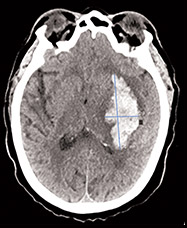

Case 1: Intracranial hemorrhage

Susan, 62*

- 7.5 mg warfarin once daily

- INR 2.3

- Afib, CKD, CHF, Diabetes, Hypertension

Use Kcentra for VKA reversal in major

bleeding cases like Susan

Use Kcentra for VKA reversal in major bleeding cases like Susan